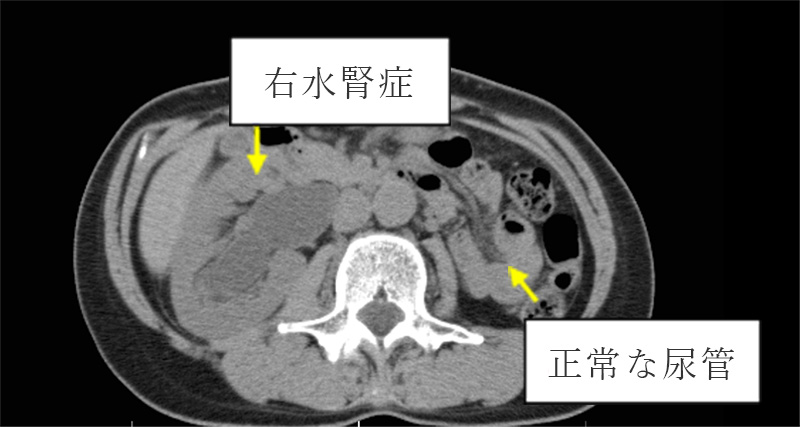

尿管結石症では尿潜血や肉眼的血尿以外に、他覚的所見として下記の示したCT画像のように水腎症、という尿管の拡張所見を認めます。

水腎症が指摘されるケースでは尿管結石症以外に尿管がんが隠れているケースもあります。特に慢性発症例や高齢者では注意が必要です。